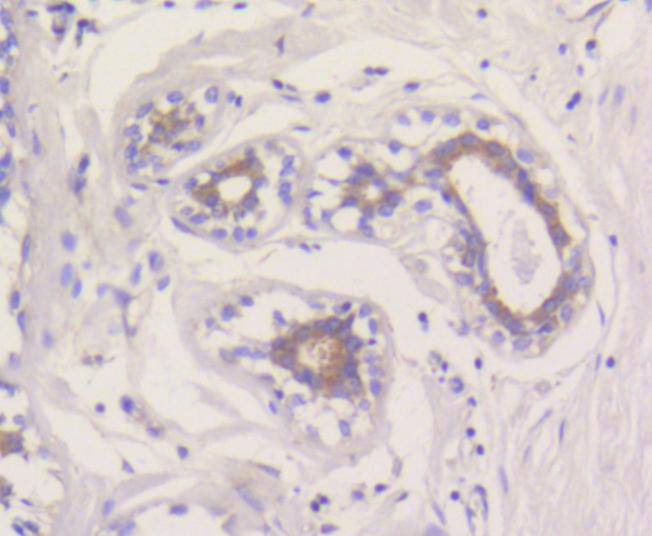

Immunohistochemical analysis of paraffin-embedded human breast tissue using anti-MCL1 antibody. The section was pre-treated using heat mediated antigen retrieval with Tris-EDTA buffer (pH 8.0-8.4) for 20 minutes.The tissues were blocked in 5% BSA for 30 minutes at room temperature, washed with ddH2O and PBS, and then probed with the primary antibody (ET1606-14, 1/50) for 30 minutes at room temperature. The detection was performed using an HRP conjugated compact polymer system. DAB was used as the chromogen. Tissues were counterstained with hematoxylin and mounted with DPX.